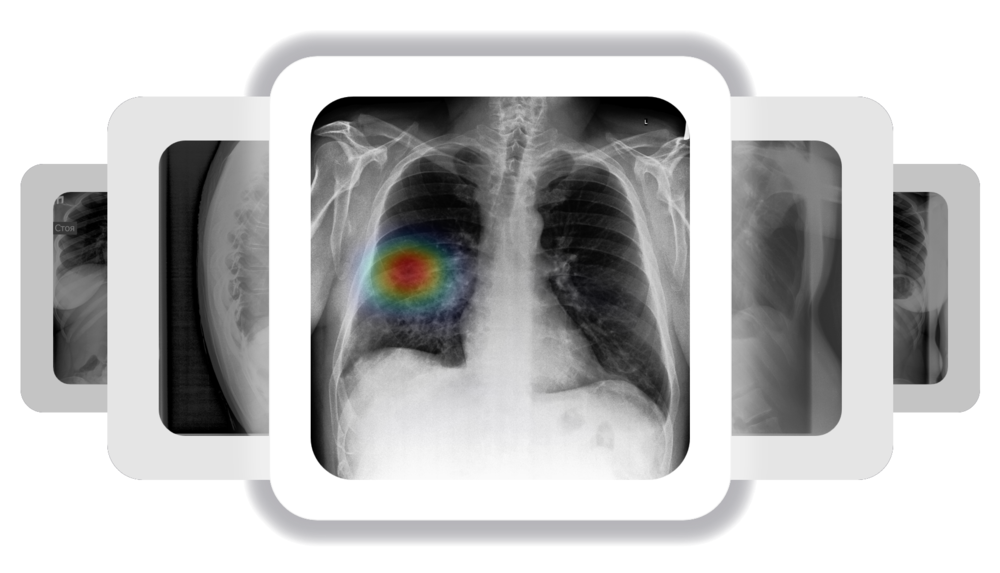

ИИ и алгоритмы интеллектуального анализа рентгеновских снимков грудной клетки. Выявление множества нарушений менее чем за 1 минуту